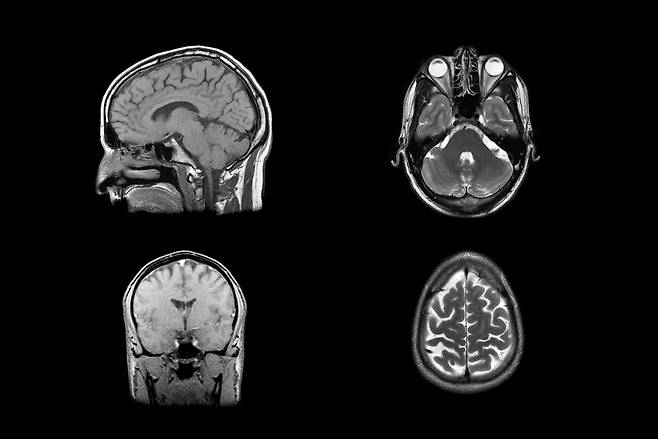

연구진은 그렇게 모인 40명의 실험 참가자들에게

서로 다른 두 가지 통증을 느끼게 한 후,

fMRI(기능성자기공명영상장치)를 통해

사람들의 뇌가 어떻게 반응하는지 관찰하기로 했죠.